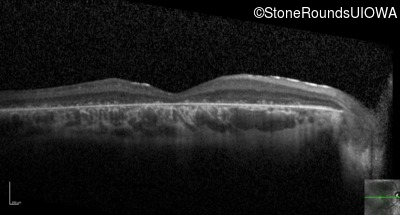

Optical Coherence Tomography - Right - 10/200

Exemplar / OCT Stack

Optical Coherence Tomography - Left - 10/160 -1